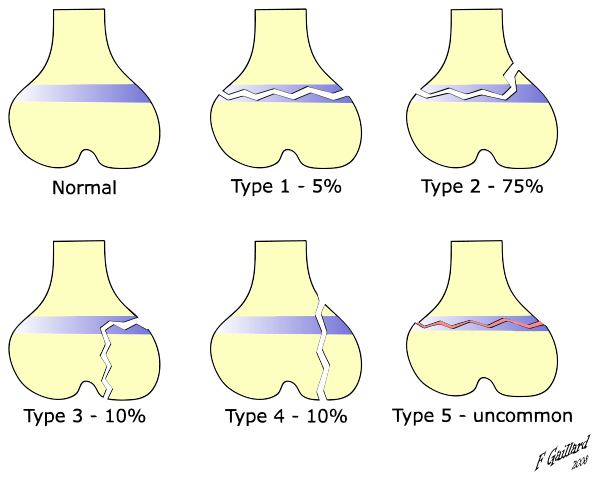

Las lesiones de las metáfisis son especialmente importantes durante el período de crecimiento. Esto es debido a su relación con la placa de crecimiento.

Alrededor de 30% de las fracturas en individuos en crecimiento involucran el cartílago de crecimiento y, de este porcentaje, se extra que el 75% tiene lesión de la metáfisis.

Las fracturas de la metáfisis que implican la lesión del cartílago de crecimiento se denominan fracturas de Salter-Harris. Estas se dividen en cinco tipos, dependiendo de los elementos que estén involucrados en la lesión y de la gravedad de la misma.

Este tipo de fracturas ocurre en niños muy activos, por lo general deportistas. Las más comunes se denominan Salter tipo II; son rupturas lineales que separan parcialmente la metáfisis y el plato de crecimiento de la epífisis.

En algunos casos es complicado observarlas claramente en una radiografía convencional. El diagnóstico se hace correlacionando el interrogatorio con el examen físico y los hallazgos radiológicos.

Las fracturas Salter tipo II son de manejo sencillo, con inmovilización y reposo, y no interfieren en el crecimiento del niño.

Estas lesiones deben ser evaluadas por un especialista, ya que cuando no se realiza el diagnóstico oportuno el paciente puede tener repercusiones en el crecimiento que no son reversibles.